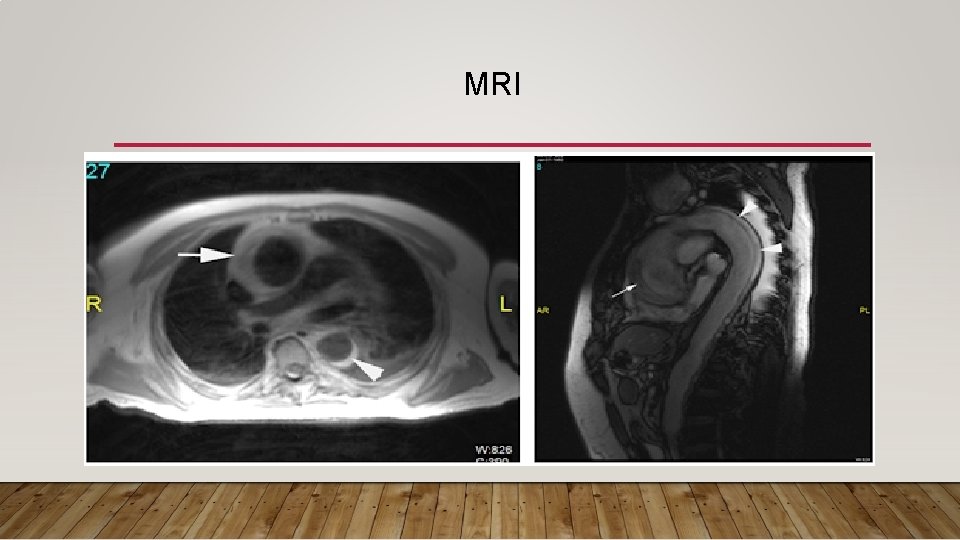

3) CT AND MRI : are both highly accurate but need stable patient , And MRI take longer to perform make it less ideal in the acute setting

MRI